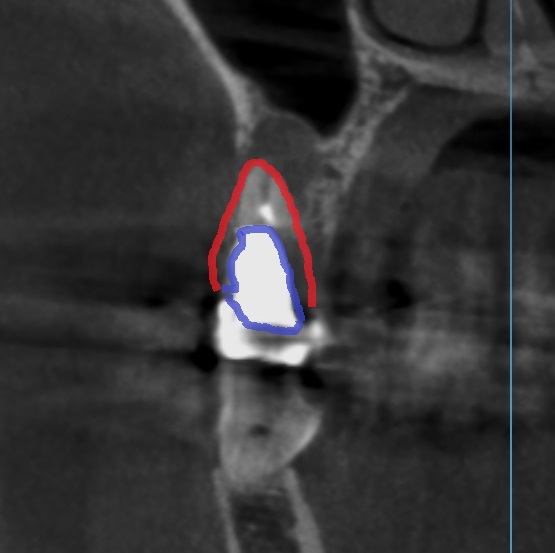

メタルコアCT画像

CT撮影で見るとこのような状態です。

メタルコアの輪郭

赤は歯の輪郭で、青がメタルコアの輪郭です。

歯の幅の7割くらいのメタルコアが入り込んでいます。